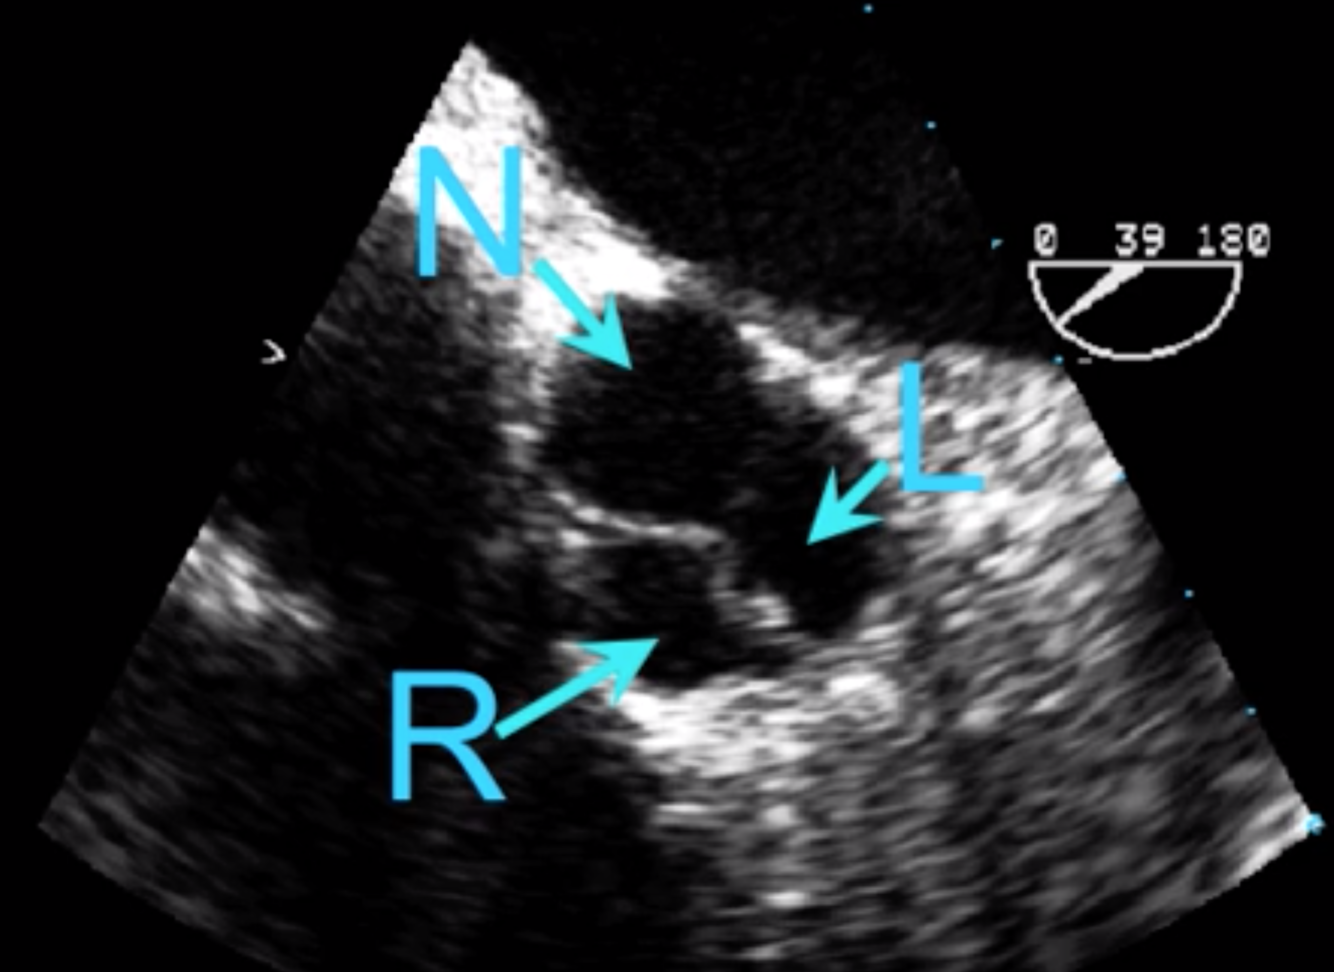

Label the Aortic Valve Cusps in the Aortic Valve Short Axis

Non-Coronary Cusp nearest to the interatrial septum (Does not have a coronary artery)

Left Coronary Cusp is NOT on the Right side

Right coronary cusp near the right heart at the bottom of the screen